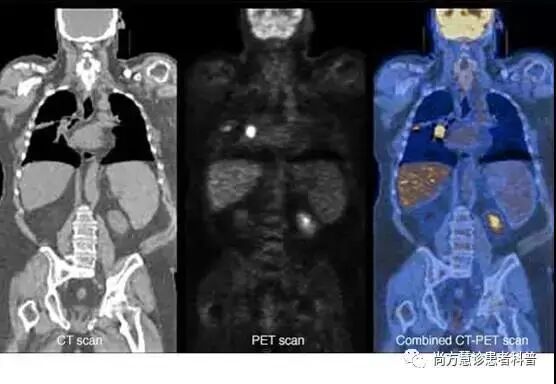

检查肺癌是否远处转移:PET或PET/CT 扫描

肺癌最先转移到胸腔内肺门和纵隔淋巴结和附近器官如胸壁等,但是肺癌也会出现远处转移,例如骨转移,脑转移和其他器官的转移,例如肝脏等。胸部CT可以检查肺癌的淋巴结和胸部的转移,脑转移只有脑部增强MRI可以诊断出来,骨转移可以通过骨扫描诊断出来,PET/CT可以诊断出除脑部之外的转移。

PET扫描:在这个检查中,一种名为FDG的放射性糖被注入血液中。因为体内的癌细胞生长很快,它们比正常脏器能吸收更多的放射性糖。这种放射性可以用特殊的照相机来观察,吸收糖比较多的部位在检查时呈现出高亮区域(医学术语叫做高代谢、高SUV值)。

PET/CT扫描:通常PET扫描与CT扫描结合使用,一种特殊的机器可以同时进行这两项工作。这使得医生可以比较PET扫描中较高放射性的部位,并在CT扫描上更详细地显示该区域。PET/CT这是最常用于肺癌患者的扫描类型。PET/CT扫描有如下作用:显示肿块的大小,肿块是否为癌症,癌症是否扩散,以及癌症都扩散到了身体哪些部位。

对疑似肺癌的病人,必要的情况下(尤其疑似晚期肺癌),医生可以通过这个检查来帮助确定癌症是否扩散到附近的淋巴结或其他部位,这有助于确定手术是否适合你,还是放化疗等更为适合。这个检查也有助于更好的了解其他影像检查出来的异常部位是否可能是癌症。

如果医生认为癌症可能已经扩散,但不知道在哪里,PET/CT扫描可以起到定位的作用。这种检查可以显示癌症是否扩散到了肝脏、骨骼、肾上腺或其他器官等。但PET/CT对脑转移的观察没有那么有用,因为所有的脑细胞都消耗大量的葡萄糖,检查结果和PET利用癌细胞吸收糖的表现相似,因此PET不能有效的判断脑转移的情况。

PET/CT扫描对肺癌的诊断有帮助,但其在检查治疗是否有效方面的作用尚未得到证实。大多数医生不推荐用PET/CT扫描作为肺癌患者治疗后常规的随访手段。